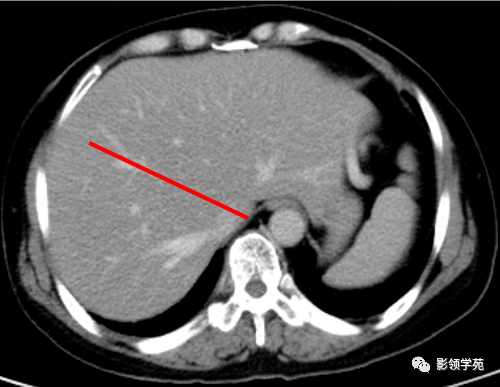

肝正中裂的超声识别

liver,肝脏;portal vein,门静脉;main lobar fissure,肝正中裂目标